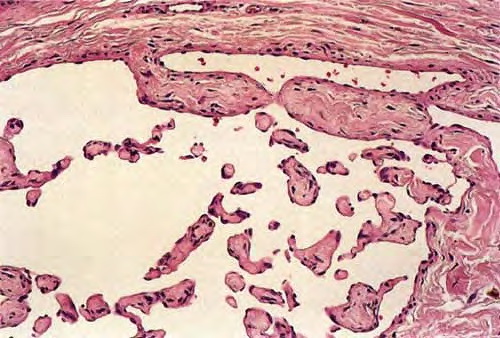

Read MoreIntravascular papillary endothelial hyperplasia = فرط تصنع حليمومي لبطانة الاوعية